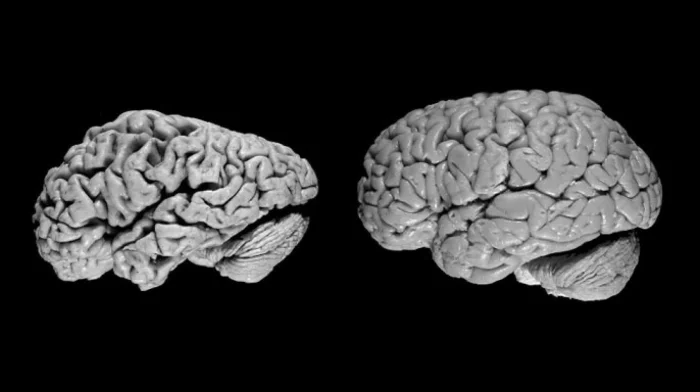

5. Опасность недосыпа

При недосыпе мозг действительно может начать "поедать" сам себя. Клетки микроглии, ответственные за очистку отходов в мозге, начинают разрушать и поглощать здоровые нейроны и связи, а не только повреждённые. Этот процесс, известный как астроцитарный фагоцитоз, усиливается при недосыпании. Со временем это может привести к проблемам с памятью, замедлению мышления и повышенному риску таких заболеваний, как болезнь Альцгеймера.